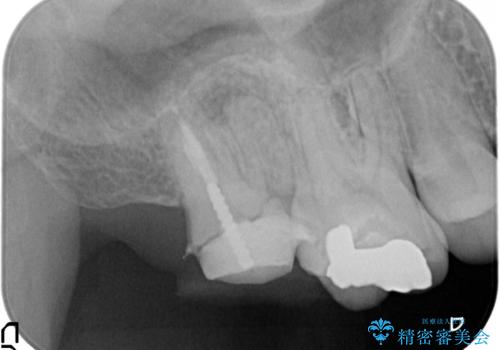

歯肉に埋もれたマージンライン 奥歯の被せもの

- 被せものが取れたことを主訴に来院されました。

以前の被せもののマージンは歯肉縁下に深く形成され、根尖病変も認めたため、根管治療(林先生に依頼)、歯周外科、PGAクラウンにて修復治療を行いました。